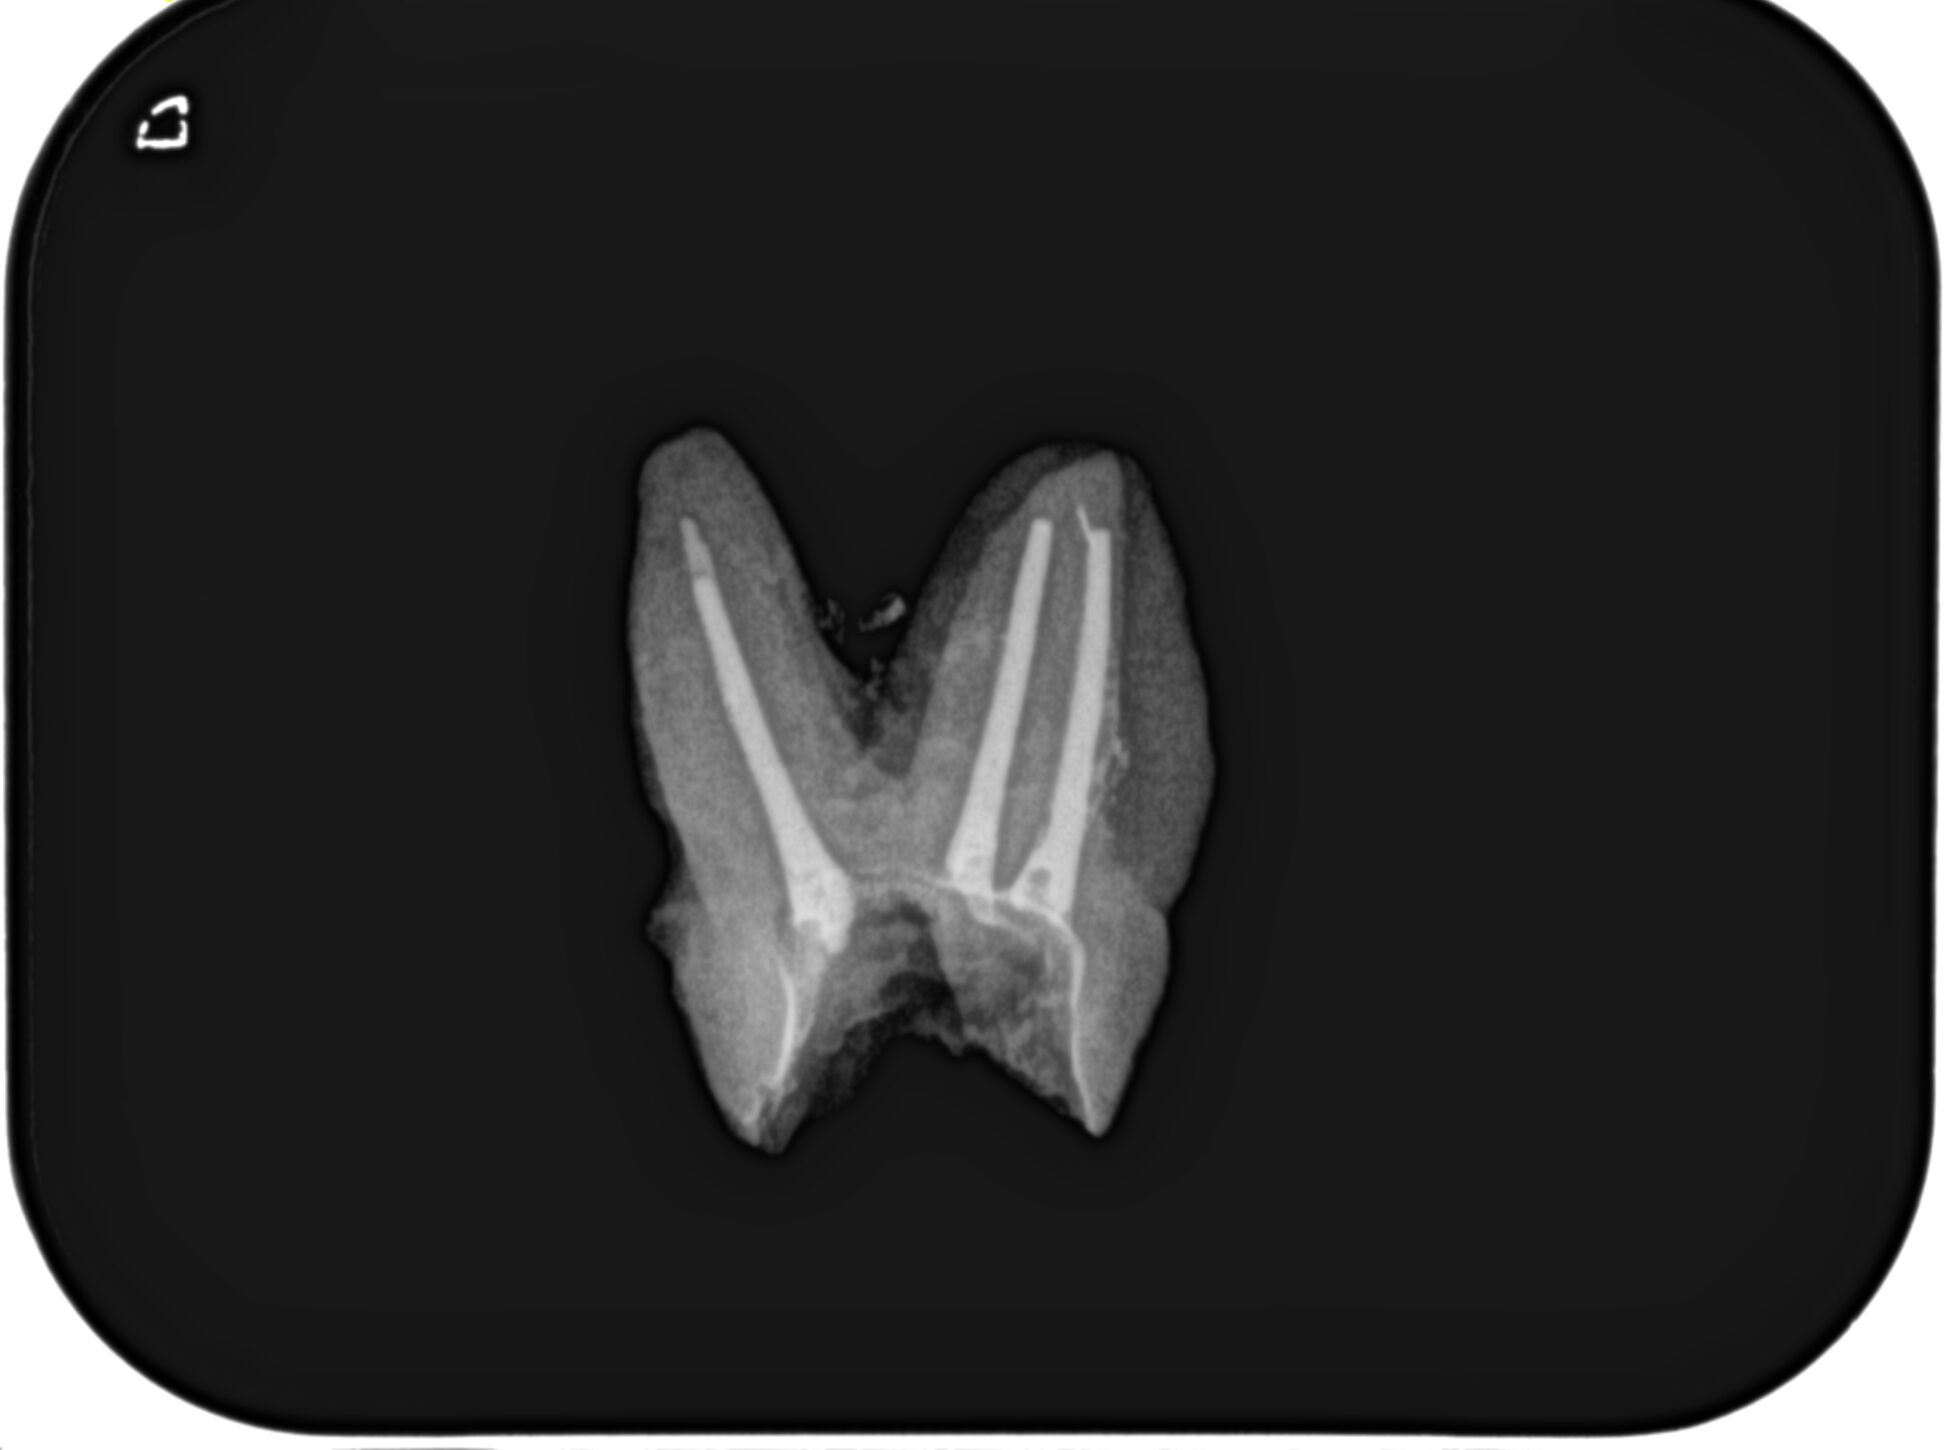

作業長を測定し、最後に再根管形成した。

その際のポイントはどこまでNi-Ti File(HyFlex EDM #25.V)が入るか?だ。

ラバーストップからReference Pointまでの距離で形成量が決まる。

その際、根尖部3mmの根管の不確実性を考慮するのであれば、

3mm以上削れる余地が残っているのであれば、#40.04が終着点でいいだろう。

が、それ以下であればHyFlex EDM #60.02かProTaper Gold F5まで形成サイズを上げるべきだろう。

それを判断する大元になるのはCBCTの分析と正しい状況の把握だ。

それにより、

HyFlex EDM #40.04で終了するか、HyFlex EDM #60.02(もしくはProTaper Gold F5)まで形成すべきか?決めれるのである。

再根管充填し、PAを撮影した。

問題はないだろう。